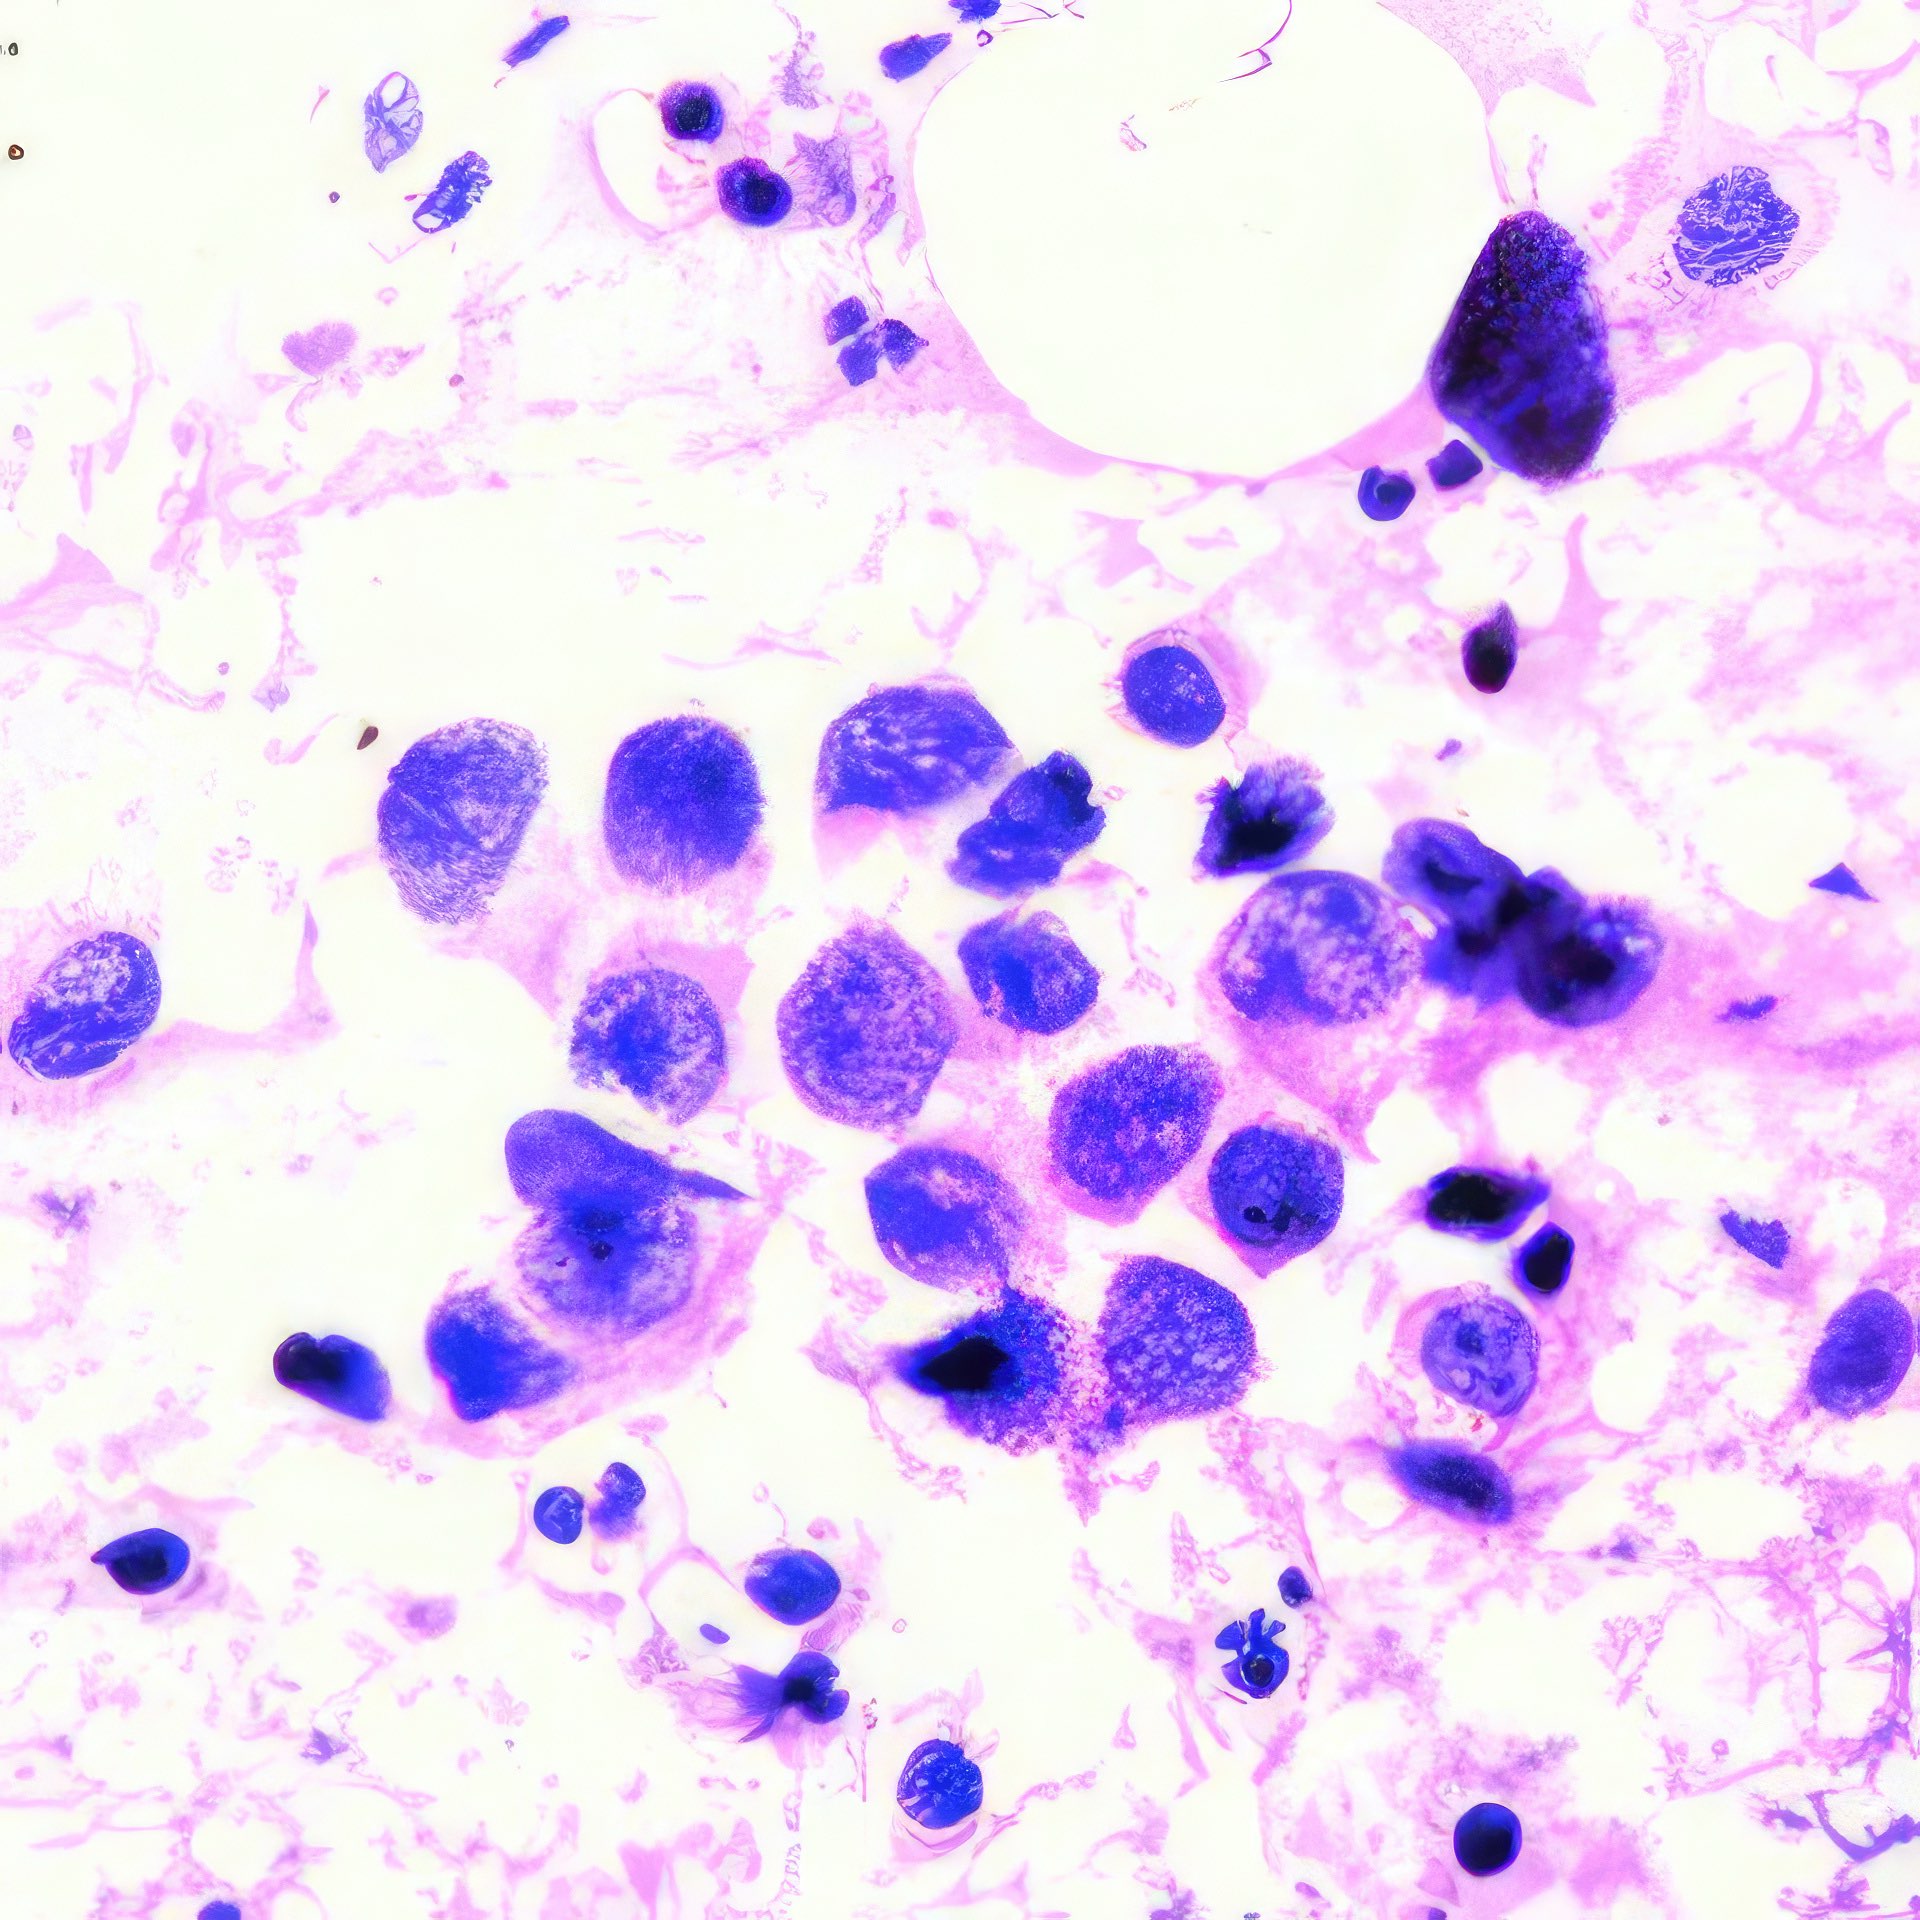

M, 55 Jahre, bemerkte seit 3 Monaten eine zunehmende inguinale Lymphknotenschwellung, der größte 3 x 4 cm messend, davon Feinnadelaspiration (FNA). Abbildung 1 bis 4: Verschiedene Areale des zytologischen Ausstrichs. Orig. 63x

Beschreibung

Die Bilder zeigen hochatypische Zellen. Deren überwiegend runde, teils auch ovalen Kerne variieren erheblich in ihrer Größe, sind deutlich grob strukturiert und enthalten meist ein oder mehrere prominente Nukleolen bzw. Chromozentren. Das Zytoplasma erscheint fragil. In jedem Bild finden sich auch Zellen mit pigmentbeladenem Zytoplasma. Der Ausstrichhintergrund enthält Blut und Zelldetritus, ebenfalls vermischt mit Pigmentkörnchen.

Kommentar

Der Patient beobachtete seit einem Jahr am Fuß eine pigmentierte Veränderung, die seit 3 Monaten auf 3 cm Durchmesser zunahm. Die prominente Atypie und die pigmenthaltigen Zellen sowie die ausgedehnte Metastasierung in die inguinalen Lymphknoten sind typisch für das Melanom. Eine Verwechslung des Melanin-Pigments mit Hämosiderin ist wegen der Zellatypie so gut wie ausgeschlossen. – Amelanotische Melanome zeigen oft eine weniger ausgeprägte Kernatypie und sind eher mit einem anderen Tumor zu verwechseln.